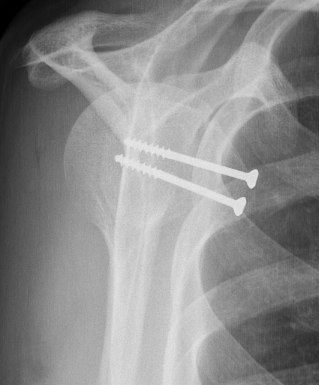

Screw fixation

LT ORIFLT ORIF